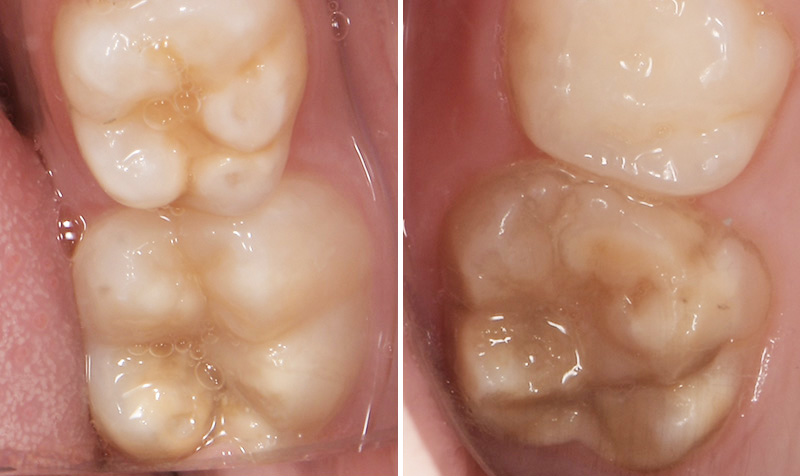

Fig. 02 : molaires atteintes de MIH (HSPM + MIH pour la figure gauche).

Cette atteinte peut être soit légère (émail blanc, opaque), soit modérée (coloration jaune, brune, surface crayeuse et effondrement post-éruptif de l’email ou PEB) ou enfin sévère (atteintes associées à des pertes de substances importantes). De plus, l’intégrité de la dent peut être aussi touchée.

Plus la MIH est sévère et plus le manque d’émail sera important donc plus les sensibilités/douleurs seront importantes aussi. Cette sévérité varie en fonction des personnes, mais également au sein des dents d’un même individu : on parle d’atteinte asymétrique. Toutes les dents ne sont pas touchées de la même façon et ne nécessiteront donc pas les mêmes types de soin.